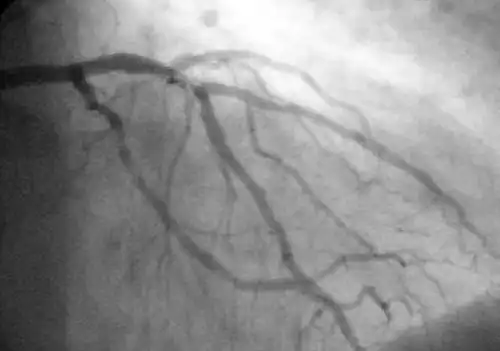

Koronarangiografie: Dargestellt wird die linke Koronararterie mit ihren Ästen.

Mit Hilfe der diagnostischen Koronarangiographie können Koronararterien dargestellt und deren Anatomie sowie das Ausmaß und die Lokalisation eventueller Stenosen beurteilt werden. Sie ist die Untersuchung mit der besten Aussagekraft. Bei dieser Untersuchung wird ein Herzkatheter über die Arteria femoralis (Oberschenkelarterie) oder seltener über die Arteria brachialis (Oberarmarterie) bis zu den Abgängen der Koronararterien aus der Aorta vorgeschoben und Kontrastmittel in die Abgänge injiziert. Mit Hilfe von Röntgenstrahlung können die Koronararterien sichtbar gemacht und beurteilt werden.[24] Der Katheter kann, unter Überbrückung der Aortenklappe, weiter in die linke Herzkammer vorgeschoben werden. Diese Untersuchung wird als Ventrikulografie bezeichnet. Sie ermöglicht zusätzlich regionale Kontraktionsstörungen sichtbar zu machen, die zum Beispiel Hinweise auf zurückliegende Herzinfarkte bieten können, sowie eine Beurteilung der linksventrikulären Pumpfunktion über Berechnung der Auswurffraktion und die Bestimmung der Dehnbarkeit der Herzmuskulatur (Compliance) durch Bestimmung des enddiastolischen Volumens.[1]